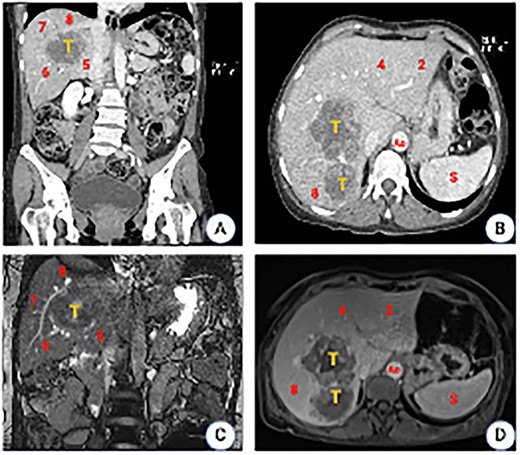

Prior to surgery, a 3D liver reconstruction image with liver volumetry was performed using a free open-source software (3D Slicer) (Fig. 2). Liver volumetry calculated the volume of the right lobe and segment 4 was 1401.2 cc (77% of the total volume) and the volume of segments 1, 2 and 3 was 418 cc (23% of the total volume), given the previous exposure to chemotherapy and an insufficient FLR with a future liver remanent/weight ratio (FLR/WR) of 0.44, it was decided to perform an extended right hepatectomy using the ALPPS technique (Fig. 3). It was calculated the Comprehensive ALPPS Preoperative Risk Assesment (CAPRA) score wich was of 3.96, with an estimated 90d mortality <7% and the pre-stage 1 ALPPS risk model of 0 points with an early mortality risk of 2.7%. The PO course was uneventful, until the PO Day 7, when the fluid drain turned milky, chylous ascites was confirmed by determination of triglyceride levels in the drainage fluid at 300 mg/dL; thus, management with medium chain fatty acids rich diet, parenteral nutrition and somatostatin analog (octreotide) was started. On PO Day 10 of treatment, there was evidence of decreased drainage volume and serous discoloration with a normalization of triglyceride fluid levels, so a normal diet was started with adequate tolerance, the liver function tests were normal at that time, and the patient was discharged on PO Day 11 (Fig. 4).

3D image reconstruction. (A) Right hemi-liver mass involving segments 5, 6, 7 and 8. The relation to the suprahepatic veins (HV), IVC and the PV is shown. (B) Future liver remnant (FLR) (Segments 2 and 3). SIVC, suprahepatic inferior vena cava; PV, portal vein; FLR, future liver remnant. (C) Liver volumetry. Coronal plane delimiting the transection line planned and the FLR. (D). Axial plane, showing the transection line planned and the FLR.